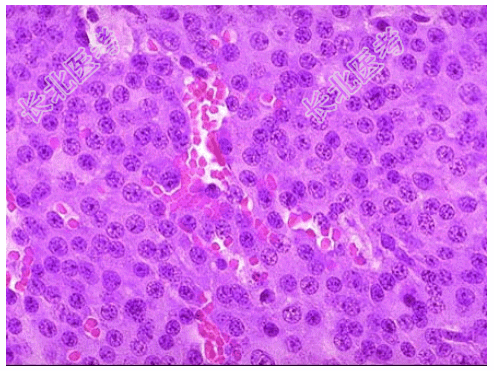

- [材料题] 患者女性,32岁,停经、泌乳,泌乳素升高为主要临床表现就诊,入院后MRI示垂体腺形态异常。手术探查见蝶鞍区一境界清楚肿物,直径大约2cm,切除送检镜下如图,临床诊断为垂体腺瘤。

- 简答题2、该疾病病理学改变表现为?